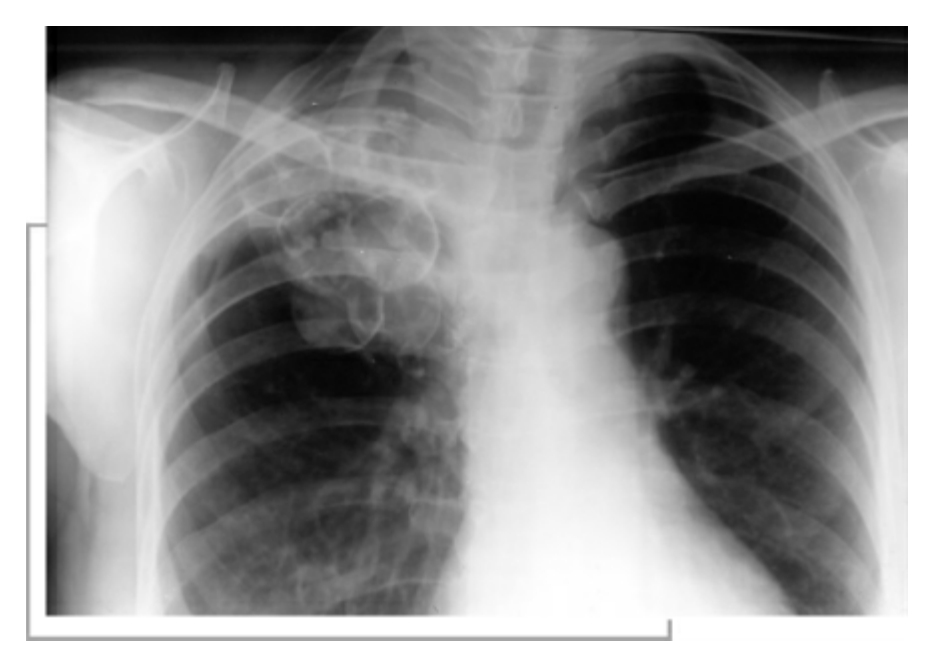

结核病患者胸部透视图

由于感染菌的毒力、数量、机体的免疫状态不同,肺结核可有分原发感染、原发后感染2类表现。